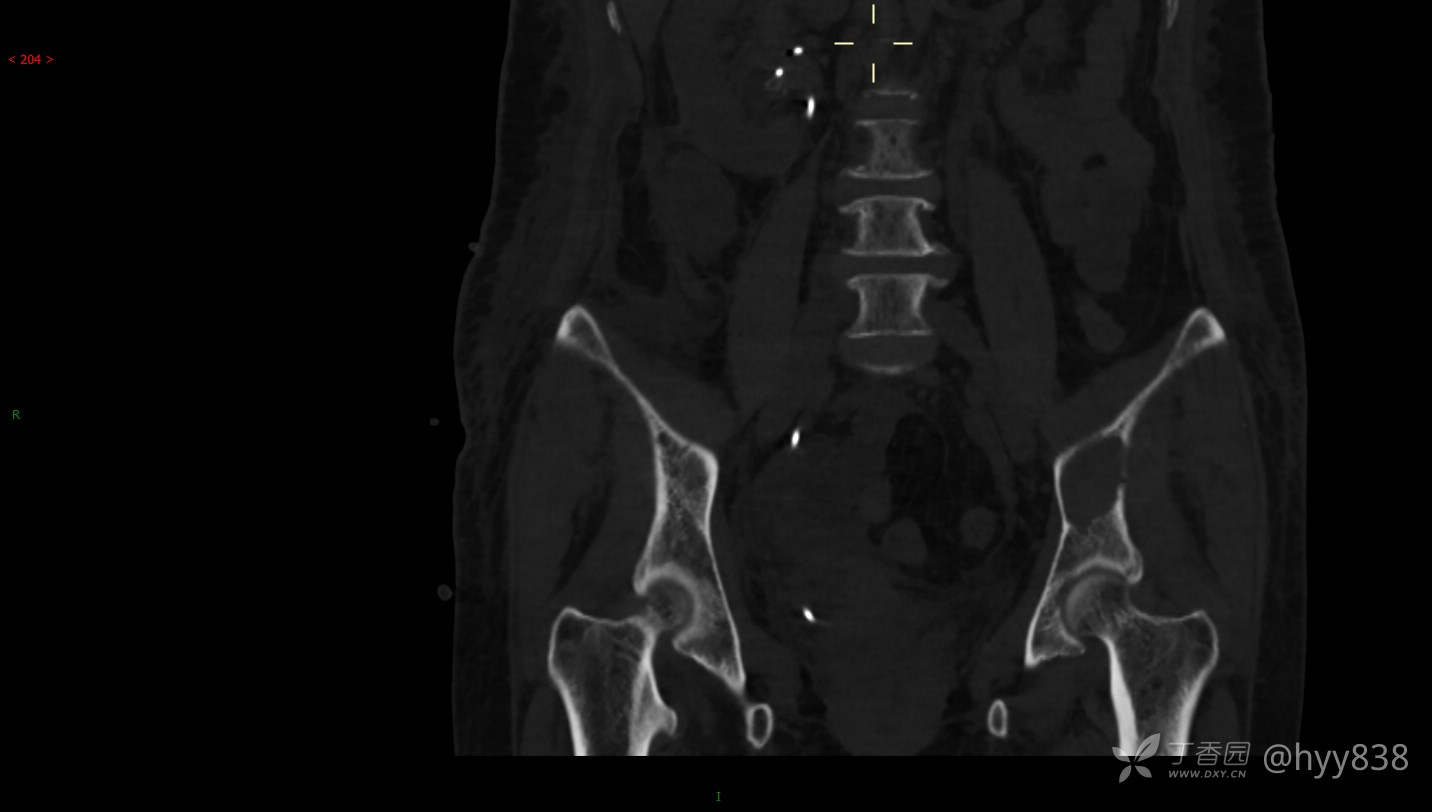

CT平扫

骨窗